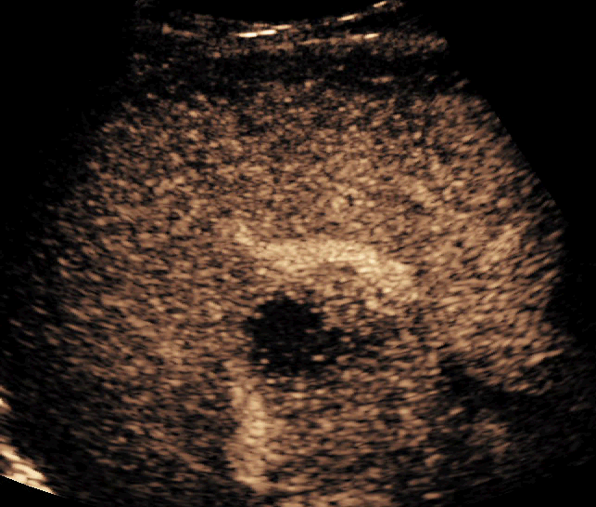

Using Siemens Healthineers ultrasound equipment, these bubbles can be imaged in two distinct contrast-based imaging modes: contrast pulse sequencing and contrast harmonic imaging.

According to Brian, “CPS has a three-pulse sequence that allows us to get deeper into the body. You can see the bubbles a little quicker and they look bigger than they would in the alternate mode. It’s going to provide a better penetration of the ultrasound, making it ideal for most scans involving adults.”

“CHI gives us a higher resolution image for evaluating smaller lesions or lesions with smaller vessels,” said Brian.

Once the procedure is in progress, the contrast goes through three distinct perfusion phases that last up to six minutes. These include the arterial, portal and late phases.

During this phase, the contrast enters the arteries of the liver to begin the imaging. Being a dynamic modality, a sonographer can capture this early flow consistently.

“The arterial phase is important for a lesion such as a focal nodular hyperplasia,” said Brian. “You'll see a central feeder artery and the vessels that branch off of it, like spokes off of a wheel.”

Missing this early phase, which can be common with other modalities, is not a concern when using contrast-enhanced ultrasound.

Once the arterial phase is complete, the ultrasound professional can begin to visualize the contrast flowing through the portal system and filling the liver.

“It is important to see both the arterial and portal phases to be able to accurately diagnose a lesion. Again, being a dynamic modality, you can visualize the flow of contrast in each separate phase without worrying about missing anything,” said Brian.

During the final phase, the liver takes in as much contrast as possible until it reaches equilibrium and starts to wash out.

“Different lesions show different filling patterns, with some lesions, such as large hemangiomas, for example, taking a long amount of time to completely fill with contrast.”

Each of these phases is very important for accurate diagnosis. Throughout the procedure, you can monitor the contrast to determine where the bubbles travel, how fast the lesion fills, how quickly it washes out, etc., all in a real-time manner. That makes this type of imaging incredibly versatile.